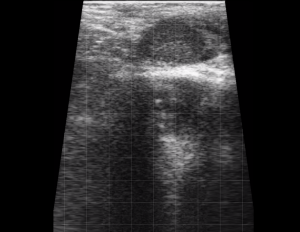

SIMON Ultrasound Database

This ultrasound database is a free resource for students and doctors!

Our collection includes videos of dogs, cats, horses, cows, humans, and many other species!